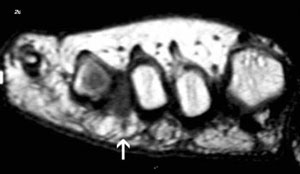

Las pruebas diagnósticas utilizadas son la ecografía y la resonancia magnética, no siendo visible en una radiografía normal.